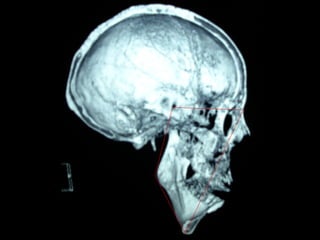

Cefalometría elementalCefalometría elemental

Se observa el número total de órganos dentarios incluyendo

terceros molares.

No hay tratamiento de conductos radiculares

Buen trabeculado óseo de tipo I

Deflección craneal 26º

Longitud craneal anterior 59 mm.

Altura posterior facial 59 mm.

Posición de rama mandibular 78º

Localización de Porión 38 mm.

Arco mandibular 30º

Longitud de cuerpo mandibular 81 mm.